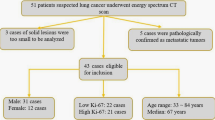

To investigate the effect of sFRP1 up-regulation on tumour imaging, we exploited the SGC-7901/vector to establish a treated group and SGC-7901/sFRP1 cells to establish a control, including T-1 (the first mouse in the treated group, pulmonary metastasis), T-2 to T-7 (the other 6 mice in the treated group, peritoneal seeding), C-1 (the first mouse in the control group, pulmonary metastasis) and C-2 to C-7 (the other 6 mice in the control group, peritoneal seeding).

Similarly, C-2 to C-7 [C3 shown in Supplementary Fig. 1] did not show any obvious positive performance with PET/CT and spectral CT [Fig. 3]. The SUVmax was approximately 0.3. However, radiological images of T-2 revealed one subcutaneous metastasis, which showed mild or moderate peripheral enhancement on DEsCT and much higher FDG uptake, with an SUVmax close to 1.2. The pathology-identified peritoneal tumours of T-2 were not differentiated from surrounding structures by DEsCT, whereas PET/CT coronal fused images depicted the focal abnormal uptake of metastases, with an SUVmax close to 0.98 [Fig. 4]. With successful peritoneal implantation, the results in the other mice (T-3 to T-7) were analogous to that of T-2, with SUVmax values of approximately 0.8, 1.06, 0.99, 0.83 and 0.96, respectively [T-3 to T-6 shown in Supplementary Figures 1,3,4 and 5]. A significant difference in the SUVmax of peritoneal metastasis was observed between the treated and control groups (P < 0.001).

Gross specimen analysis demonstrated a nodule in C-1 that was 0.8 mm in diameter [Fig. 1]. Two metastatic nodules in the T-1 gross specimen were 4.1 and 3.2 mm in diameter, respectively, which was consistent with findings using PET-CT images (4.27 mm and 3.45 mm, respectively). The lesion in the inferior lobe of right lung is shown in Fig. 2, whereas the other lesion on the left side was not visible in this image. C-2 to C-7 showed four to ten nodules on the peritoneum, with 3.1 mm being the largest in size by gross specimen. The average size of peritoneal nodules from C-2 to C-7 was 1.13 mm (ranging from 0.5 mm to 3.1 mm). T-2 to T-7 revealed 8 to 21 peritoneal lesions with 6.11 mm as the largest size confirmed by gross specimen (mean 2.66 mm, ranging from 0.6 mm to 6.11 mm). Additionally, T-2 showed another subcutaneous lesion, with 13.6 mm as the largest size. No significant difference in tumour number was shown between the treated and control groups (P = 0.528). For the peritoneal tumour size, there was a significant difference between the treated and control groups (P < 0.001). Therefore, the treated group showed an increasing average size of tumours in C-3 and other positive radiological images in T-3 to T-6 [see supplementary results].

After imaging, all tumours were dissected for further analysis. Histology and TUNEL were performed to measure apoptosis in the tumour tissue. TUNEL analysis showed that there were fewer apoptotic cells in tumours formed by sFRP1-overexpressing cells than by control cells [Fig. 5C]. Immunohistochemical staining revealed that tumours derived from sFRP1-overexpressing cells contained more proliferative cells (assayed by Ki-67 staining) and more microvessels (assayed by CD34 staining). We next tested whether the supernatant of sFRP1-overexpressing cell cultures promoted angiogenesis in vitro. We found that the supernatant of sFRP1-overexpressing cells indeed induced more tubular formation of HUVECs compared with control supernatant, demonstrating the angiogenic effect of sFRP1 in vitro [Fig. 6A]. Likewise, supernatant from sFRP1-overexpressing cells induced more HUVEC migration compared to supernatant from vector control cells. [Figure 6B]. sFRP122 and ID123 have been reported to increase tumour vessel density as well as the expression of vascular endothelial growth factor (VEGF), a well-known angiogenic factor induced by tumour growth factor β signalling24. Indeed, higher levels of VEGF were found in the culture supernatants of sFRP1-overexpressing cells compared to control cells [Fig. 6C, left].

Great efforts have been put forth to show that FDG uptake is associated with tumour aggressiveness25. Progressive gastric carcinomas, represented as the depth of invasion, lymphatic permeation, vascular invasion and tumour size, showed higher FDG uptake26. In this study, the increasing number and larger size of tumours in the treated group demonstrated an increase in tumour aggressiveness. Consistently, the treated group with higher aggressiveness presented a positive performance, in contrast with the control group. In terms of quantitative evaluation, studies suggested that the SUVmax (one of the most popular candidates for semi-quantitative analysis of tumour glucose metabolism) has a positive correlation with proliferation in various malignancies27,28. Ki-67 was utilized as a quantitative biomarker for tumour aggressiveness, reflecting invasiveness and metastatic potential29,30. A significant moderate correlation coefficient was observed between SUVmax and the Ki-67 proliferation index (PI)25,31. The generation of a lethal tumour mass requires both tumour cell proliferation and angiogenesis32. Glucose metabolism was increased to supply sufficient energy for proliferation, leading to increased FDG accumulation in tumours with high growth rates, which explained the mechanism at cellular level33. In our study, the immunological analysis consistently demonstrated that sFRP1 overexpression resulted in increased cell proliferation and decreased apoptosis.